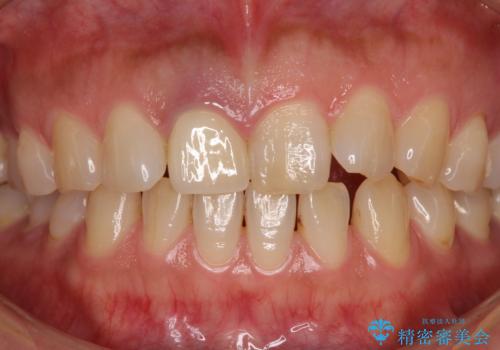

- セラミッククラウンが白すぎる前歯と、放置している奥歯を気にして来院された患者様です。

前歯のセラミッククラウンは将来ホワイトニングをするつもりで白くしたものの、それほど白くならず、ホワイトニングも面倒くさいとのことで白すぎる印象となっていました。

前歯のセラミッククラウンは周りの歯と調和させるためにオーダーメイドタイプのものをおすすめしましたが、元が白すぎていたため、概ね色合いが合えば大丈夫であるとのことで、既製パターンの色調で仕上げました。